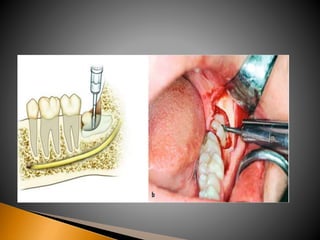

 5 passosbásicos que compõem a técnica: 1. Exposição adequada do dente (retalho) 2. Remoção óssea 3. Odontosecção 4. Remoção do dente 5. Alisamento do osso e irrigação

• 81.

1. Quantidade deosso removido 2. Odontosecção (avaliar a necessidade e a quantidade) 3. Remoção excessiva de osso(conseqüências)

• 82.

 A dificuldadeda remoção de um dente impactado depende da sua acessibilidade.  O retalho mucoperiosteal da área onde vai ser feita a remoção do osso de recobrimento do dente impactado deve ter uma dimensão adequada ou suficiente para permitir a colocação e a estabilização de afastadores e instrumentos para remoção de osso.

• 84.

 O maisusado é o retalho em envelope, que é mais fácil para fechar e tem uma melhor cicatrização comparada ao retalho de três ângulos.

• 85.

 É oretalho em envelope com uma incisão de alívio, contudo se o cirurgião dentista necessitar de um acesso maior em regiões mais apicais, onde pode ocorrer dilaceração do retalho em envelope ocorrida pela força de tensão, deve-se então considerar o uso do retalho de três ângulos.

• 86.

 A incisãopara remoção de terceiros molares inferiores e superiores é o envelope, mas se o terceiro molar inferior esta profundamente submerso no osso e requer uma remoção mais ampla do mesmo, uma incisão de alivio pode ser útil (retalho de três ângulos).  A incisão deve ser planejada de forma que possa ser fechada sobre o osso íntegro. Isto é obtido pela extensão pelo menos um dente anterior ao sitio cirúrgico quando uma incisão de alivio for usada. A incisão deve evitar estruturas anatômicas vitais, somente uma incisão de alivio deve ser usada.

• 87.

 Após otecido mole ser elevado e rebatido, fazendo com o que o campo cirúrgico seja visualizado, o cirurgião deve fazer um julgamento em relação a quantidade de osso a ser removido. Em alguns casos o dente pode ser seccionado com uma broca e removido sem retirada de osso. Porem na maioria dos casos alguma remoção óssea é requerida.

• 89.

 O ossona face oclusal é removida primeiro para expor a coroa do dente. A broca pode ser usada para remover, o osso entre o dente e a cortical óssea na área medular do osso, por meio de uma manobra chamada canaleta.  Para dentes superiores a remoção óssea é quase sempre desnecessária, mas quando preciso o osso é removido , primeiramente, na face vestibular do dente, abaixo da linha cervical, para expor a coroa clinica inteira.